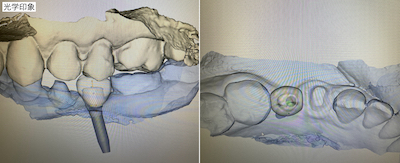

リハビリ後に光学印象を行いました。

自身のインプラント埋入の再評価を行い、補綴物の設計を行いました。1週間後にカスタムアバットメントとセラミックを装着しました。